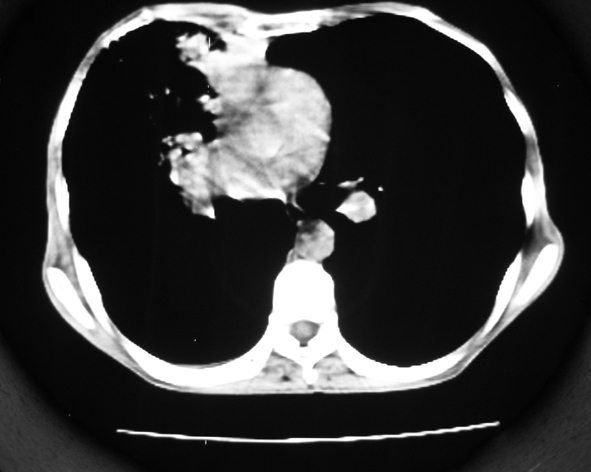

男53岁,咳嗽气短,以往身体健康.

右肺上叶多发多形态空洞及增殖灶,可见团块钙化,胸膜肥厚、粘连,考虑继发型肺结核可能性大

1.右肺上叶干酪性肺炎,2。肺气肿,肺大泡

右肺上中叶结核干酪性肺炎

右肺中上叶干酪性肺炎。